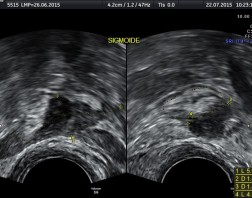

Ultrassonografia Pélvica transvaginal com preparo intestinal prévio (pesquisa de endometriose)

Exame realizado via vaginal, com a bexiga vazia, onde o transdutor (aparelho introduzido suavemente na vagina) tem um calibre fino, adequado para o exame, e é protegido por preservativo. Neste exame faz-se a avaliação dos órgãos genitais internos (útero e ovários) quanto a sua normalidade, identificando eventuais patologias. Além disto, buscam-se sinais visíveis à ultrassonografia que podem se relacionar com endometriose, bem como seu grau de profundidade de acometimento. Sabe-se, porém, que principalmente os casos de endometriose leve podem não ser identificados.